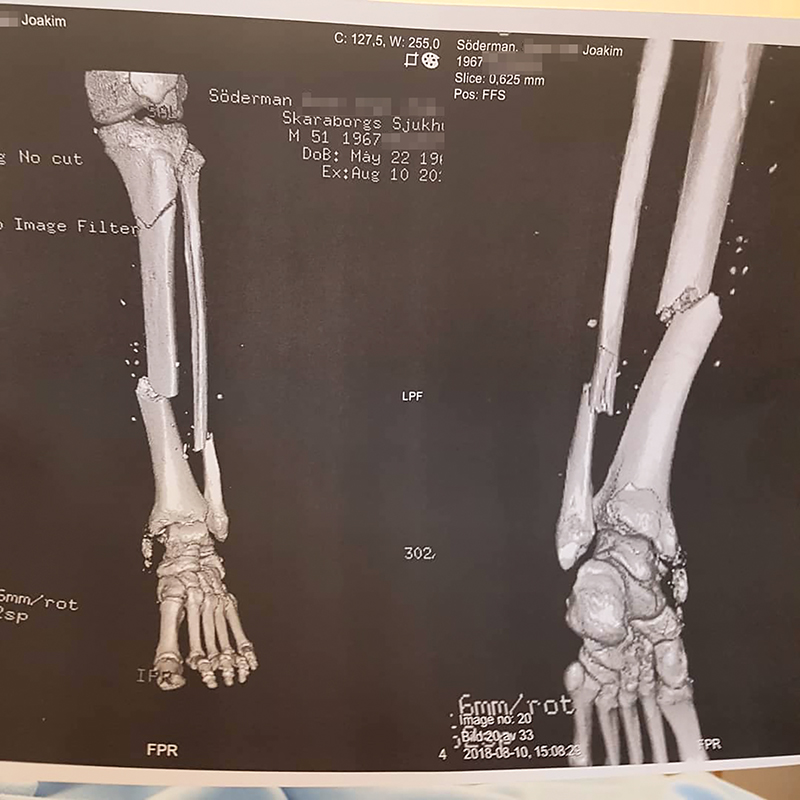

Nu har Försäkringskassan sagt sitt baserat på läkarintyget som beskriver ”omfattande underbensfrakturer, omfattande fotledsfrakturer samt omfattande, öppna fotfrakturer”. Sistnämnda har alltså inte läkt än.

Två av totalt 16 frakturer vill inte läka. Men enligt Försäkringskassan kan Joakim Söderman ändå jobba.